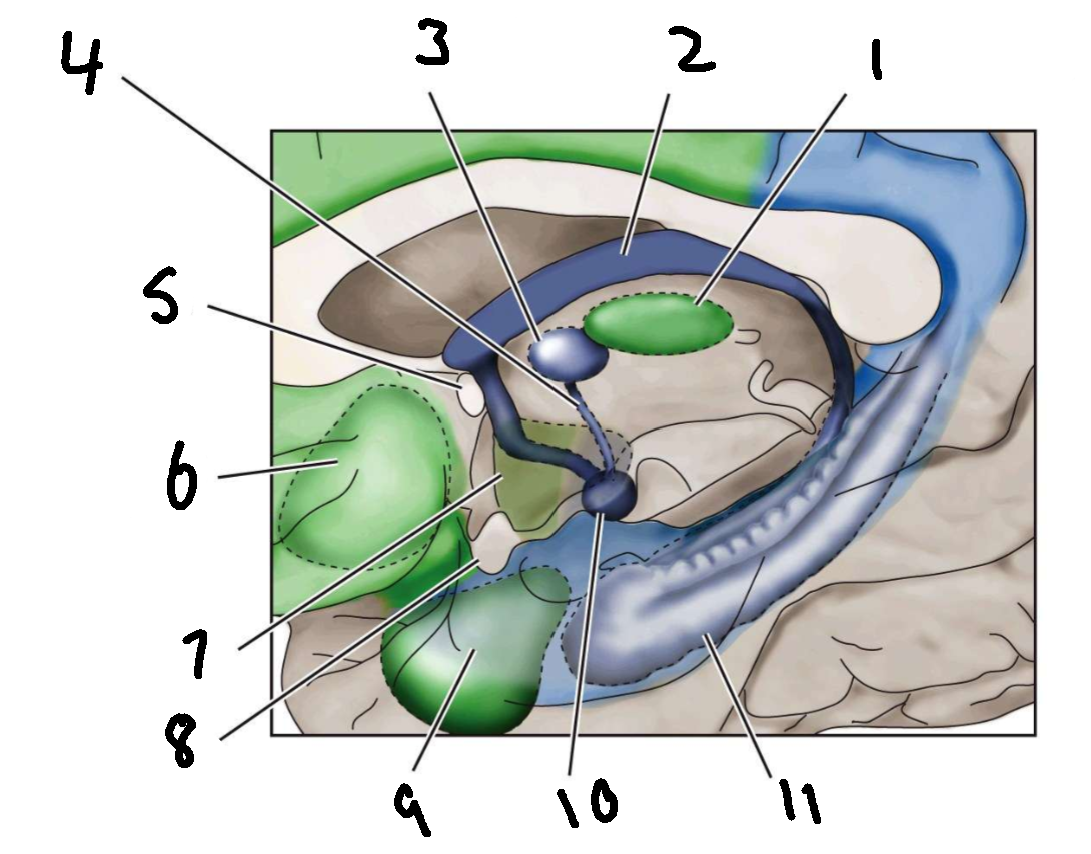

What is 1?

mediodorsal nucleus of the thalamus

What is 2?

fornix

What is 3?

anterior nucleus of the thalamus

What is 4?

mammillothalamic tract

What is 5?

anterior commissure

What is 6?

ventral basal ganglia

What is 7?

hypothalamus

What is 8?

optic chiasm

What is 9?

amygdala

What is 10?

mammillary body

What is 11?

hippocampus